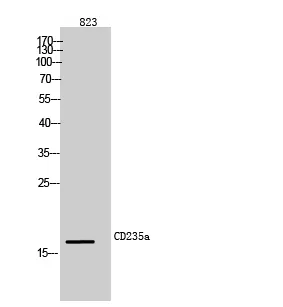

CD235a Rabbit Polyclonal Antibody

Cat: APRab08295

Size1:50μl Price1:$118

Size2:100μl Price2:$220

Size3:500μl Price3:$980